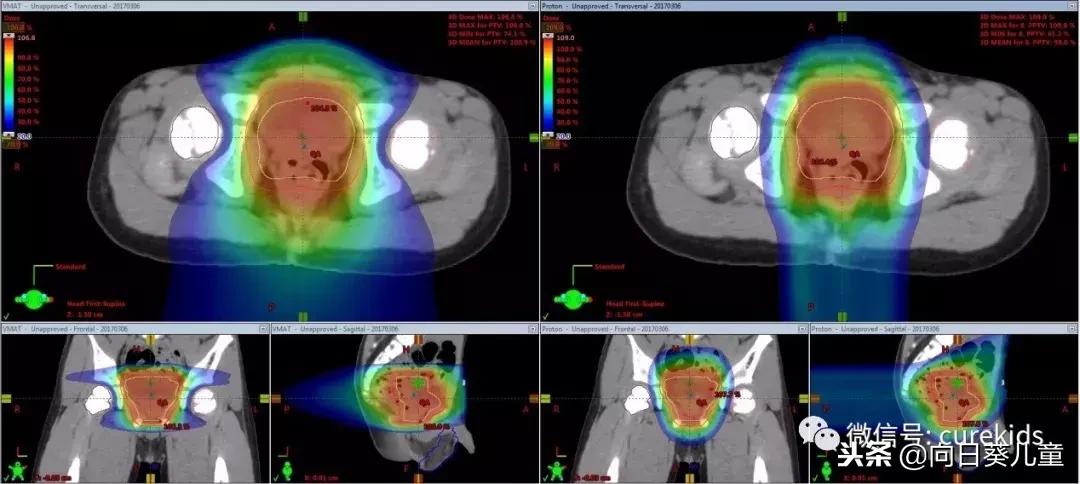

我们来看一个比较对照图,这是一个患有膀胱横纹肌肉瘤的孩子,右侧是用质子射束治疗,左侧是弧型调强多照野光子治疗。

从图上看,黄色区域是要治疗区域,蓝色区域是中高剂量区域,因为这个区域在盆腔外围,旁边就是大腿腿骨部分,所以对一个年纪比较小的患儿来说,无论使用哪种治疗方式,都要尽量避开大腿的骨头关节部分,保护骨关节,减小以后对孩子行走的影响。